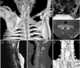

Sprengel's deformity (also known as high scapula or congenital high scapula) is a rare congenital skeletal abnormality where a person has one shoulder blade that sits higher on the back than the other. The deformity is due to a failure in early fetal development where the shoulder fails to descend properly from the neck to its final position. [Source: Wikipedia ]